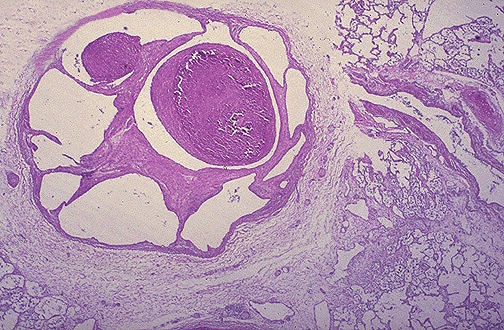

The fibrous bands of connective tissue across this branch of pulmonary artery indicate organization of a remote pulmonary thromboembolus. If many pulmonary arteries are involved by this process, pulmonary hypertension could result.